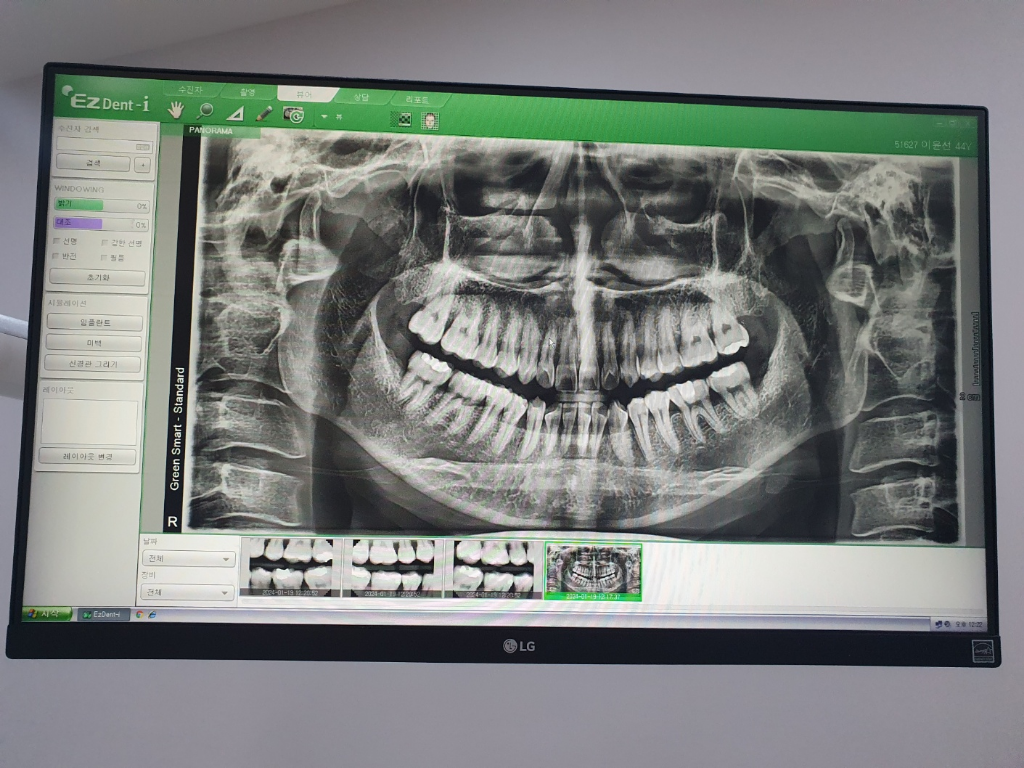

엑스레이 상으로 보면 오른쪽아래 어금니 뒤쪽으로 충치가 잇는것처럼 보입니다. 그리고 씹을떄 통증이 잇다면 치아에 금이갓을 가능성도 잇으니 통증이 지속되면 치료를 받으셔야될수도 잇을것같습니다.

보철물을 제거해봐야 확실하겠지만 충치가 있는 것으로 보입니다. 통증이 지속되면 치료받으러 가셔야 겠습니다.